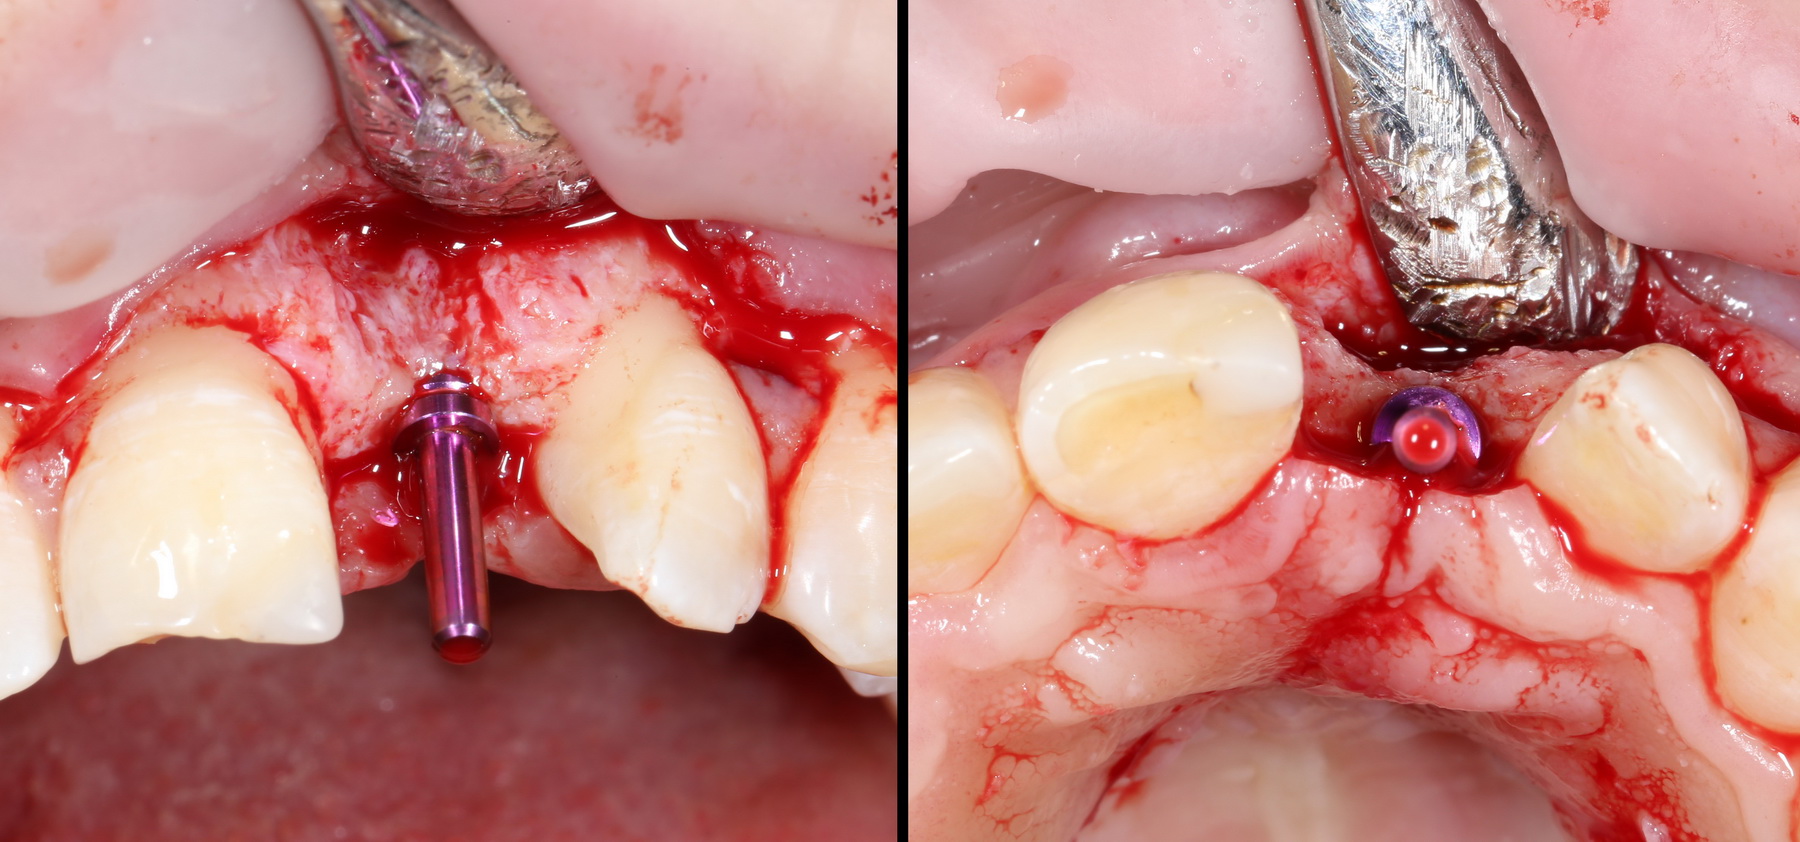

Итого, наиболее оптимальным в данной ситуации оказалась направленная тканевая регенерация с использованием барьерных мембран. В качестве барьерной мембраны у нас будет Geistlich BioGide. Ее очень легко адаптировать и позиционировать:

А в качестве трансплантата — аутокостная стружка, которую я насобирал заранее из области угла нижней челюсти:

Начну с того, что BioGide — это лучшее, что есть сейчас на рынке, а остальные мембраны ей завидуют. Как и в случае с макродизайном имплантов, именно физические свойства определяют как удобство использования, так и возможность достижения нужного результата. Прочность, эластичность, легкая адаптация и адгезия делают ненужными использование фиксирующих пинов. Мы просто закрываем мембраной графт — и все, можно накладывать швы:

В другом ракурсе видно, какой объем тканей мы восстанавливаем:

и теперь швы. Наглухо (Фактор II):

Вот так мы сочетаем имплантацию с остеопластикой. И, если мы сделали все по правилам и без противоречий здравому смыслу, то через 3 месяца мы должны получить неплохой результат.